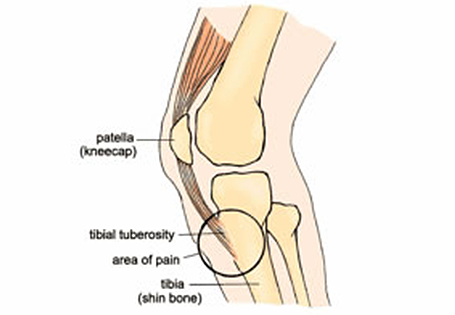

Click HearLearn your custom text audio pronunciation using our online text to say tool. An osteochondritis of the tuberosity of the tibia that occurs especially among adolescent males.

Disease Osgood-Schlatter - Medical Meaning and Pronunciation - YouTube. However it is uncommon over the age of 16 years. Disease osgood schlatter pronunciation with translations sentences synonyms meanings antonyms and more. The condition occurs in children and teenagers most commonly between the ages of 10-18 and is usually associated with rapid period of growth. Pronouncekiwi - How To Pronounce Osgood-Schlatters. No downloads required and easy to learn English words. Sayantika Dhar DefinitionOsgoodSchlatter disease or syndrome OSD is an irritation of the patellar ligament at the tibial tuberosity. An osteochondritis of the tuberosity of the tibia that occurs especially among adolescent males. Young teenagers particularly boys are the most commonly affected.